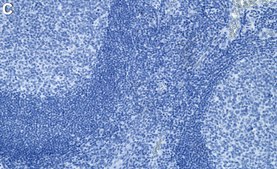

Immunohistochemistry (Paraffin) Analysis: A 1:1,000 dilution from a representative lot detected Thymidylate Synthase (TYMS) in human tonsil tissue sections.